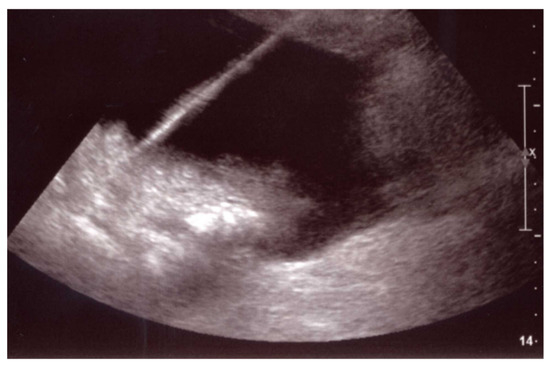

- Venturini, M.; Sallemi, C.; Marra, P.; Palmisano, A.; Agostini, G.; Lanza, C.; Balzano, G.; Falconi, M.; Secchi, A.; Fiorina, P.; et al. Allo- and auto-percutaneous intra-portal pancreatic islet transplantation (PIPIT) for diabetes cure and prevention: The role of imaging and interventional radiology. Gland. Surg. 2018, 7, 117–131. [Google Scholar] [CrossRef]

- Venturini, M.; Angeli, E.; Maffi, P.; Fiorina, P.; Bertuzzi, F.; Salvioni, M.; Cobelli, F.D.; Socci, C.; Aldrighetti, L.; Losio, C.; et al. Technique, complications, and therapeutic efficacy of percutaneous transplantation of human pancreatic islet cells in type 1 diabetes: The role of US. Radiology 2005, 234, 617–624. [Google Scholar] [CrossRef]